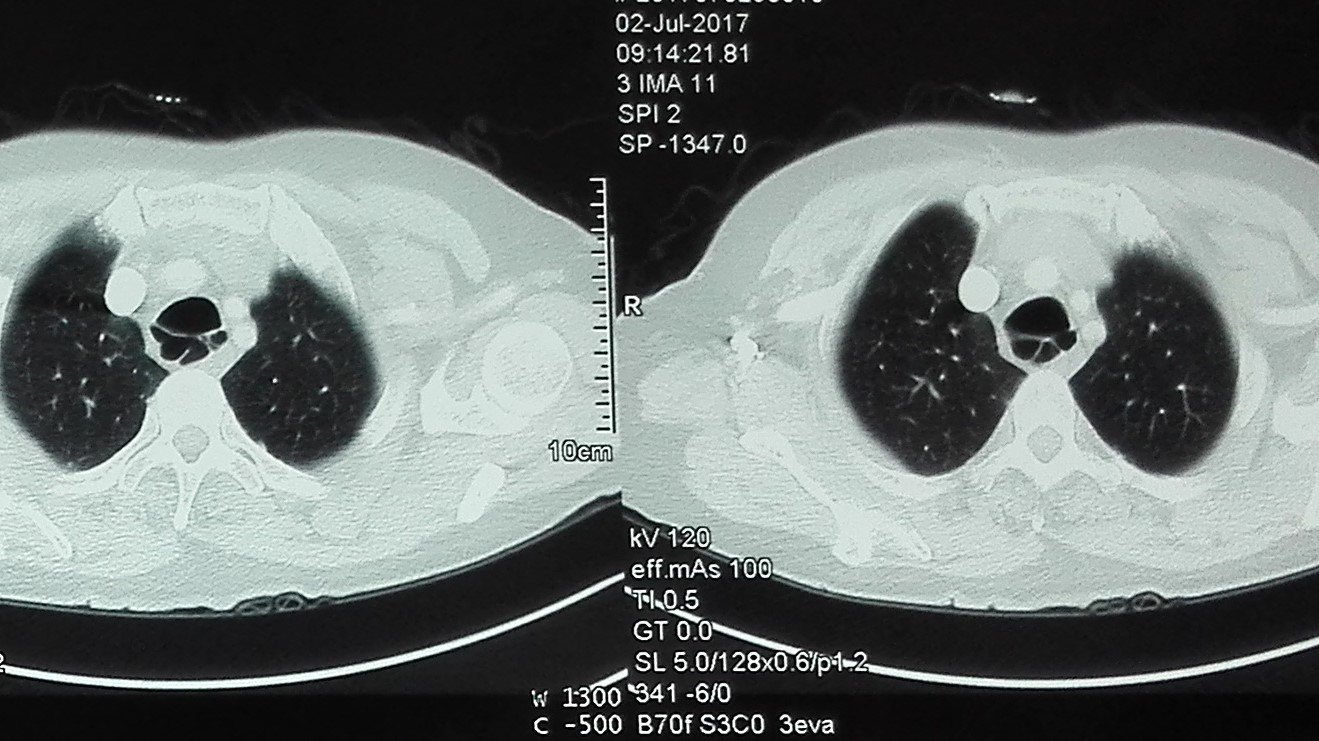

下面是一些典型憩室ct表现的分享:总结一下,气管憩室,是良性的先天性

刘懿博士说肺癌一〇九九新长出来的气管憩室需要做